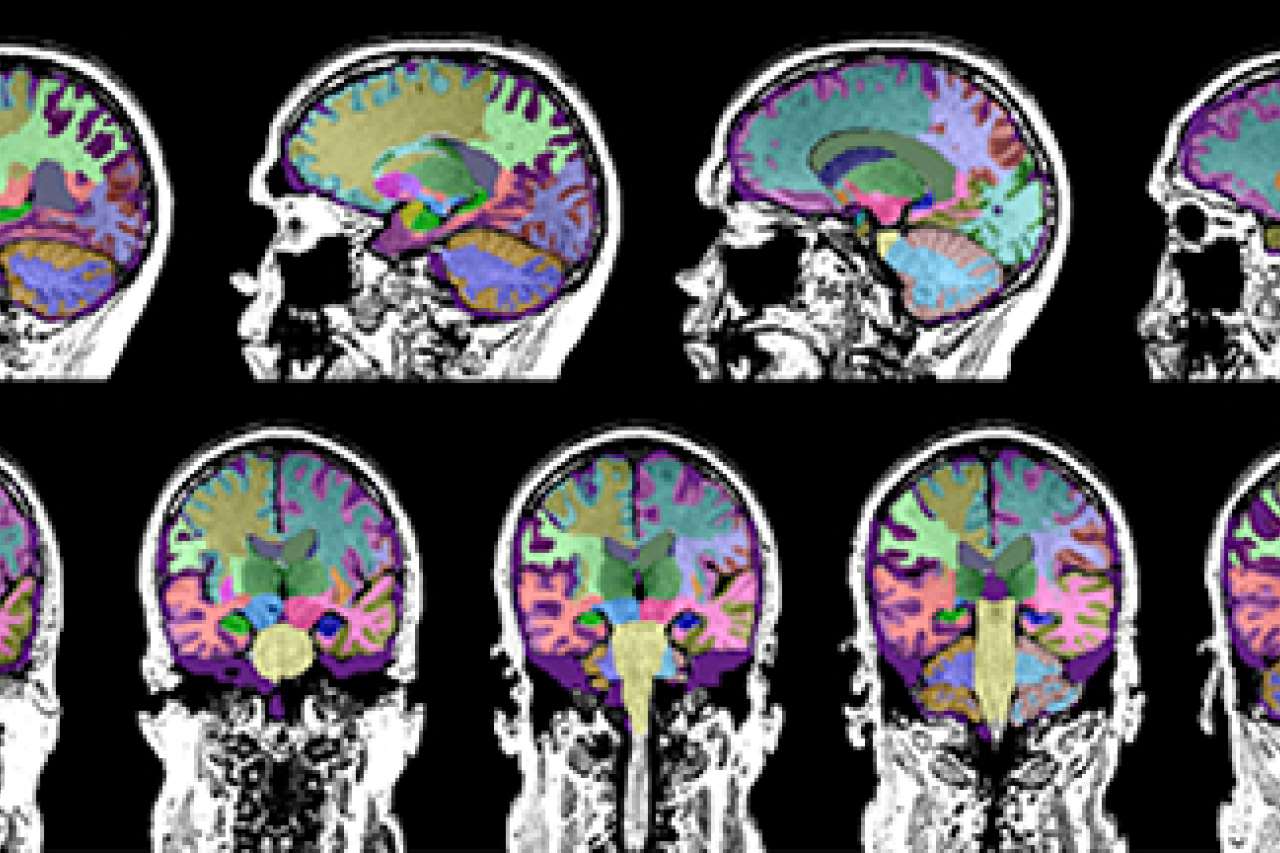

from brainreader.net

Brain volume loss measured from magnetic resonance imaging (mri) is a marker of neurodegeneration. when there is brain volume loss, it’s called atrophy. parenchymal volume loss is a term in the field of medical imaging, indicating the reduction in the volume of. this typically refers to what is visible on an mri brain scan as “white patches” in the white matter structures of the brain, as seen on specific imaging. brain atrophy may be present in tbi with visually apparent volume loss and encephalomalacia in moderate and severe cases. Everyone loses brain volume after the age of 40, so just because you see the.

Progressive Focal Gray Matter Volume Loss in a Former High School What Does Volume Loss Mean On A Brain Mri Everyone loses brain volume after the age of 40, so just because you see the. Brain volume loss measured from magnetic resonance imaging (mri) is a marker of neurodegeneration. when there is brain volume loss, it’s called atrophy. brain atrophy may be present in tbi with visually apparent volume loss and encephalomalacia in moderate and severe cases. . What Does Volume Loss Mean On A Brain Mri.